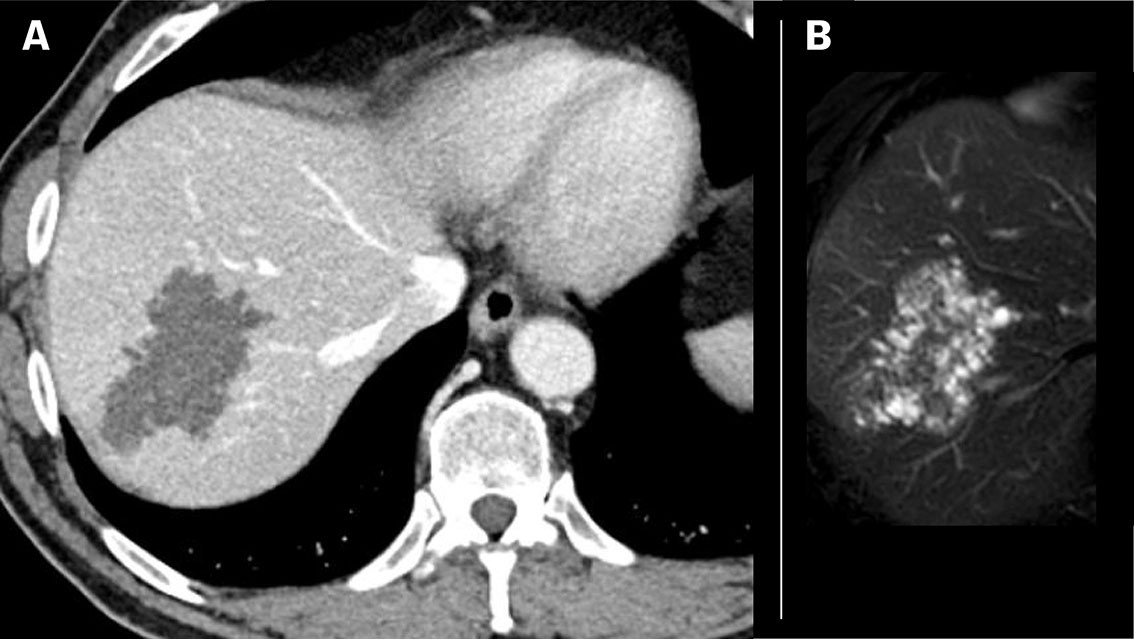

Pasient 1: En mann i 30-årene fra Øst-Europa som hadde bodd flere år i Norge, utviklet ikterus og smerter under høyre kostalbue. CT abdomen avdekket en 13 cm stor uregelmessig lavattenuerende forandring med sentral nekrose og forkalkninger i leversegmenter 6 og 7, mens MRCP-undersøkelse viste at alle affiserte leversegmenter var gjennomsatt av små cyster (figur 1). Serologi påviste antistoffer mot E. multilocularis, og det ble startet behandling med albendazol per os. Han ble operert med en omfattende reseksjon av høyre lever. Makropatologi bekreftet en stor multilokulær cyste (figur 2), og histologisk undersøkelse påviste cyster med laminerte membraner, nekrose og fibrose. Radikaloperasjon var ikke teknisk mulig, og det var restforandringer omkring leverhilus og retroperitonealt. Pasienten er derfor forespeilet livslang behandling med albendazol.

Diagnostikk ved alveolær ekinokokkose baseres på en kombinasjon av typiske radiologiske funn og positiv serologi. Endelig diagnose stilles ved histopatologisk undersøkelse og/eller PCR-analyser av operasjonsmateriale. Alveolær ekinokokkose klassifiseres radiologisk etter funn på CT (Alveolar Echinococcosis Ulm Classification for Computed Tomography, AEUC-CT) og MR (Kodamas klassifikasjon) (3, 4). På CT fremstår forandringene ofte som uskarpt avgrensete lobulerte oppfylninger med uregelmessig sentral nekrose og spredte forkalkninger suspekt på malign tumor, mens de karakteristiske mikrocystiske komponentene fremkommer tydeligere på MR (figur 1 og 3). MR egner seg best for karakterisering samt lokoregional utbredelse. Diagnosen stilles vanligvis ikke basert på bildediagnostikk alene, da flere andre fokale leverlesjoner, inklusive premaligne og maligne tumorer, kan ha lignende karakteristika (5). FDG PET er nyttig ved initial diagnostikk, samt for postoperativ monitorering og ved mistanke om residiv (6).